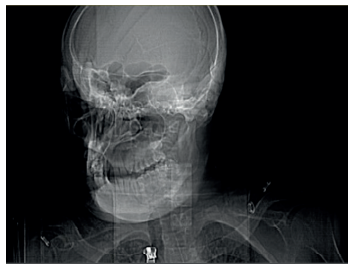

Dismorfias

A pesar de ser menos llamativas que en los otros tipos de MPS, también se puede observar cejas prominentes, pestañas oscuras, pelo grueso, hipertricosis, dolicocefalia, labios con una morfología característica (labio inferior grueso) o alteraciones morfológicas en el cartílago auricular. Los rasgos se exageran con la edad18.

En el trabajo publicado sobre alteraciones dentofaciales de Drazewski y cols.41 concluyeron que las dimensiones intermaxilares no fueron estadísticamente diferentes entre los tipos de MPS. Sin embargo, la altura y la longitud de la mandíbula fueron claramente menores en MPS I en comparación con MPS II y MPS III. Esto se asoció con la reabsorción progresiva de los cóndilos mandibulares en MPS I, que también se observó en MPS II y VI, pero no en MPS III o IVa. En cambio, la anchura mandibular fue significativamente menor en los individuos con MPS I, siendo el grupo que presentaba menor bruxismo. Debido a la parafunción, sumado a la hiperactividad de movimientos involuntarios de estos pacientes, se producen fracturas y desgastes de las superficies dentarias que pueden erosionar la mucosa oral, por lo que deben pulirse las superficies afectadas de manera meticulosa y, en casos extremos, convendría realizar la extracción dentaria.